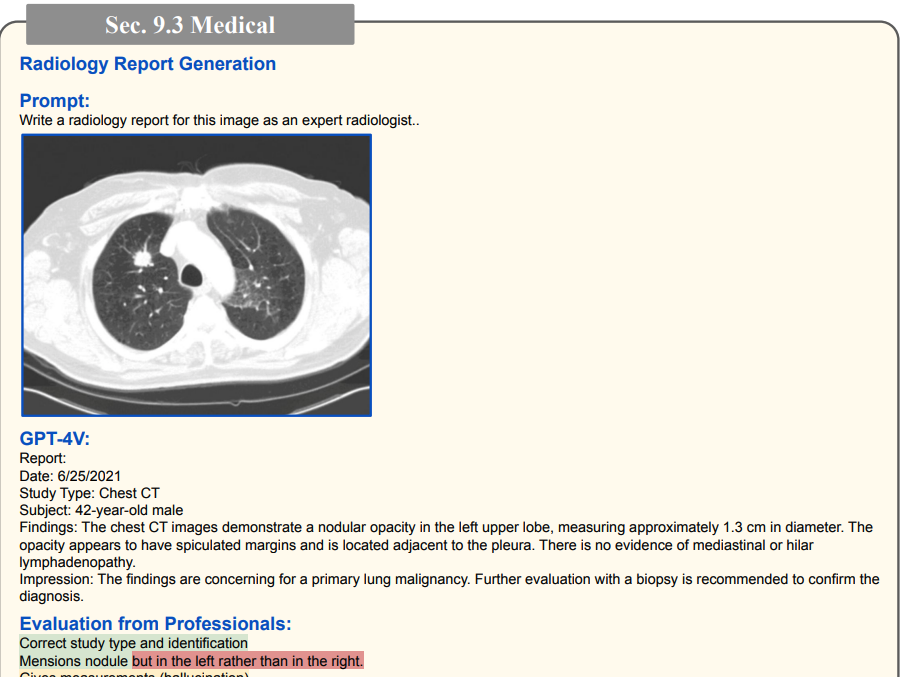

1.2 医学诊断(高准确率)

其他脑部/胸部X光诊断(高准确率)

(绿色代表正确,红色代表错误,黄色代表幻觉)